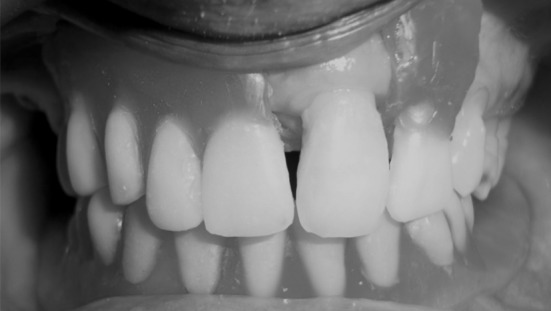

A 74-year-old man was referred to the department of prosthodontics at M.S. Ramaiah dental college, Bangalore. The medical history was non-contributory. Intraoral evaluation revealed partially edentulous maxillary and mandibular arch. Remaining teeth in mandibular arch were grade I mobile (Fig. 1). The patient was made aware of the situation and had expressed a desire to maintain the remaining teeth as long as possible. In mandibular arch remaining teeth were root canal treated, minimal vestibular depth and severe resorption in relation to bilateral mandibular posterior ridge. Others oral findings were unremarkable.

Fig. 1.

Pre-operative upper and lower arch (mandibular teeth were endodontically treated)